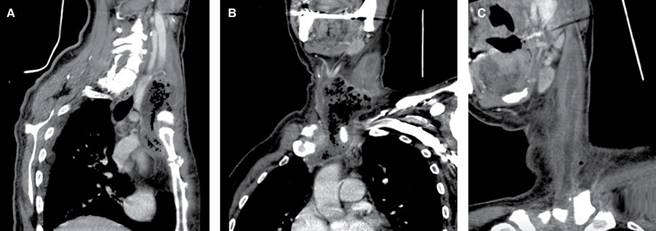

Masculino de 60 años de edad con diabetes mellitus de cinco años de evolución no controlada, sin otros antecedentes, relata presentar fiebre y faringitis de 15 días, acompañada de dolor en cuello, faringe, oído izquierdo y región retroauricular izquierda; manejado por facultativo con AINE y antibiótico no especificado, llegando el dolor a ser intolerable por lo que acude a la institución; a la exploración física: signos vitales normales, fiebre de 38.5 oC; eritema en cara anterolateral izquierda de cuello, dolor intenso en 10/10 en escala visual análoga (EVA 1-10) a la palpación de lóbulo izquierdo de tiroides, con irradiación a cara anterior de tórax, región supraclavicular y oído izquierdos; resto de exploración normal. Se ingresa, los exámenes de laboratorio mostraron: leucocitosis de 27,000/mm3 con 89% de polimorfonucleares, perfil tiroideo normal y glucosa de 320 mg/dL. Se inició antibióticos empíricos con linezolid 600 mg IV BID, meropenem 1 g IV TID, clindamicina 300 mg IV QID y control de glucosa con esquema de insulina. Se efectuó ultrasonido de cuello (Figura 1) encontrando: lesiones hiperecoicas con tendencia a la confluencia, extendidas en y alrededor del lóbulo tiroideo izquierdo. La tomografía computarizada mostró: presencia de burbujas en la glándula tiroides y a través de los tejidos blandos cervicales hacia el mediastino superior (Figuras 2 y 3). El tránsito esofágico con trago de bario no reportó presencia de fístula. A los dos días de su ingreso se encontró aumento de volumen del lóbulo izquierdo de tiroides; se efectuó punción guiada por ultrasonido, extrayendo escaso líquido seropurulento para cultivo con resultado de Staphylococcus aureus, a los seis días de hospitalización los leucocitos descendieron a 11,000/mm3. Después de 14 días de tratamiento, con mejoría clínica del dolor, de la glucemia y disminución de leucocitosis, manteniéndose el perfil tiroideo dentro de límites normales, se solicitó nueva tomografía (Figura 4) que mostró persistencia de absceso, por lo que se programó cirugía, drenando material purulento, postoperatorio sin problema; a un mes de postoperatorio, paciente asintomático, con ultrasonido de control normal al igual que perfil tiroideo.

Figura 2: (A) reconstrucción sagital de tomografía axial computarizada. Se observan burbujas de gas en topografía de la glándula tiroides que disecan a través de los tejidos blandos cervicales hacia el mediastino superior posterior a la fascia cervical media. (B) Reconstrucción coronal que revela imagen heterogénea e irregular con extensión mediastinal a través del espacio visceral.

Figura 4: Imágenes de tomografía computarizada de absceso tiroideo. (A) Reconstrucción sagital oblicua, con la extensión retroestenal desplazando la glándula tiroides en sentido posterior. (B) Reconstrucción coronal oblicua mostrando: colección compleja por gas y reforzamiento parietal por el contraste, estando involucrada la articulación esternoclavicular izquierda. (C) Reconstrucción curva, con extensión del absceso a lo largo del músculo esternocleidomastoideo ipsilateral.